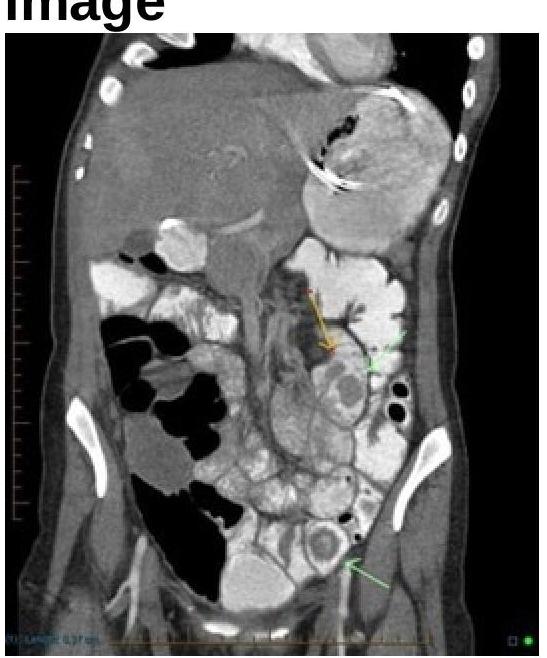

Identify the condition shown in the image.

Explanation: ***Juvenile polyp*** - The image shows **dilated, cystically appearing glands** within an inflamed lamina propria, which is characteristic of a juvenile polyp. - Juvenile polyps are the most common cause of **rectal bleeding** in children under 10 years of age and are typically benign. *Villous adenoma* - Villous adenomas are **neoplastic polyps** with a **villous (finger-like) architecture** and are more commonly seen in older adults [1]. - They typically show **dysplastic changes** and are considered premalignant [1]. *Vascular malformation* - Vascular malformations consist of **abnormally formed blood vessels** (e.g., arteriovenous malformations, hemangiomas) and would appear as dilated or aberrant vessels on histology. - While they can cause bleeding, the image does not show a predominance of vascular structures. *Serrated adenoma* - Serrated adenomas are characterized by **sawtooth-like glandular infoldings** and show varying degrees of dysplasia. - They are typically found in adults and are considered premalignant, not benign growths usually found in children. **References:** [1] Cross SS. Underwood's Pathology: A Clinical Approach. 6th ed. Common Clinical Problems From Alimentary System Disease, pp. 371-372.